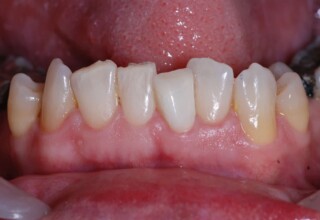

Restoration of bilateral diastemas between central and lateral incisors.

Diastemas were created mainly because of narrow laterals. After orthodontic treatment was finalized, the diastemas were closed with two composite resin restorations.